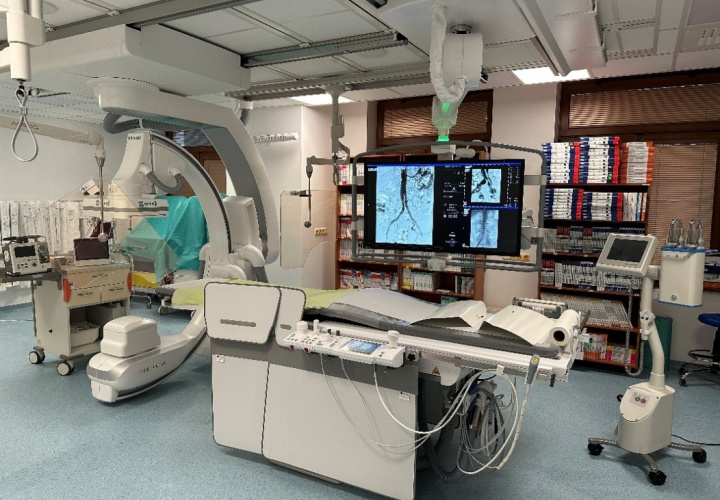

Oddelenie rádiológie má nové intervenčné pracovisko

V Stredoslovenskom ústave srdcových a cievnych chorôb a.s. pomôže pacientom s cievnymi ochoreniami nový angiografický systém ARTIS Q od spoločnosti Siemens Healthineers. Prístroj, ktorý nahradil už zastaralý systém staršej generácie, je určený na diagnostiku a liečbu ochorení ciev v celom anatomickom rozsahu s výnimkou ciev srdca. Nachádza sa v nových, moderných priestoroch pracoviska intervenčnej rádiológie a bude slúžiť hlavne pacientom s aterosklerotickým postihnutím (upchávaním) ciev, výduťami ciev, pacientom s cukrovkou, u ktorých hrozí amputácia končatiny, ďalej pacientom s rozsiahlou hlbokou žilovou trombózou a pľúcnou embóliou.

Stredoslovenský ústav srdcových a cievnych chorôb patrí k vedúcim centrám v endovaskulárnej liečbe výdutí a disekcií aorty na Slovensku. Prístroj vďaka integrovanému intravaskulárnemu ultrazvuku a najmodernejšiemu softwarovému vybaveniu, vrátane 2D/3D navigácie a fúzie s CT obrazom, ďalej posúva možnosti terapie a umožní bezpečnejšiu liečbu aj tých najkomplikovanejších prípadov.

Choroby ciev postihujú veľkú časť obyvateľstva a predpokladá sa, že ich výskyt bude v nasledujúcich rokoch výrazne stúpať. Nový angiograf vďaka špičkovej technológii skráti čas vyšetrenia pacienta, výrazne zredukuje radiačnú dávku a aj objem podanej kontrastnej látky pri zachovanej najvyššej kvalite zobrazenia. Okrem plánovaných zákrokov zaisťuje pracovisko intervenčnej rádiológie aj nepretržitú 24 hodinovú príslužbu pre akútne neodkladné stavy.

Slávnostné otvorenie tohto nového intervenčného pracoviska bolo dňa 2.2.2024 aj za účasti pani ministerky zdravotníctva Zuzany Dolinkovej.

Nový prístroj si našiel okamžité uplatnenie v liečbe komplexných ochorení aorty.

Pacient s výduťou brušnej aorty a panvových tepien ošetrený miniinvazívne cez malý rez v slabine pomocou špeciálnej cievnej protézy, ktorá umožňuje zachovať tok aj do vnútornej panvovej tepny. Pomocou 3D navigácie a fúzie s CT obrazom sa skrátil celkový čas implantácie a výrazne zredukovala radiačná dávka aj objem podanej kontrastnej látky.

Pacient s objemnou výduťou hrudnej aorty s krátkou implantačnou zónou ošetrený za pomoci 3D navigácie hrudným stentgraftom a fixovaný pomocou endoskrutiek za účelom zabránenia neskorej migrácie (posunu) graftu.